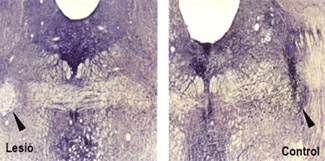

Regulació energètica als espermatozoides

Investigadors de la Facultat de Veterin�ria han aprofundit en la comprensi� dels mecanismes que utilitzen els espermatozoides dels porcs per a obtenir i regular la seva energia. La recerca mostra que el proc�s est� regulat, principalment, per l'activitat d'un enzim, l'hexoquinasa, i pel...

Espermatozoide